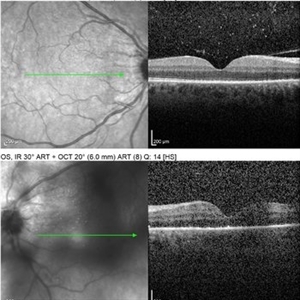

Multimodal Imaging of a Type 3 Retinal Racemose Hemangioma

Multimodal Imaging of a Type 3 Retinal Racemose Hemangioma

Sep 8 2024 by Maria Antonia Orrego

We present the case of a 33 year-old woman with visual loss of her left eye since childhood. Fundus examination revealed a retinal arteriovenous malformation with vessels originating from the optic nerve and extending to the fovea and equator, corresponding to a type 3 retinal racemose hemangioma (A). Infrared reflectance imaging confirmed findings described in funduscopy (B). Spectral domain optical coherence tomography shows dilated vessels in the internal and external retinal layers and adjacent intraretinal fluid (C).

Photographer: Dr. Maria Antonia Orrego V, Universidad CES, Clinica Clofán, Medellín, Colombia

Imaging device: Optovue Solix

Condition/keywords: arteriovenous malformation, multimodal imaging, racemose hemangioma, retinal arteriovenous malformations